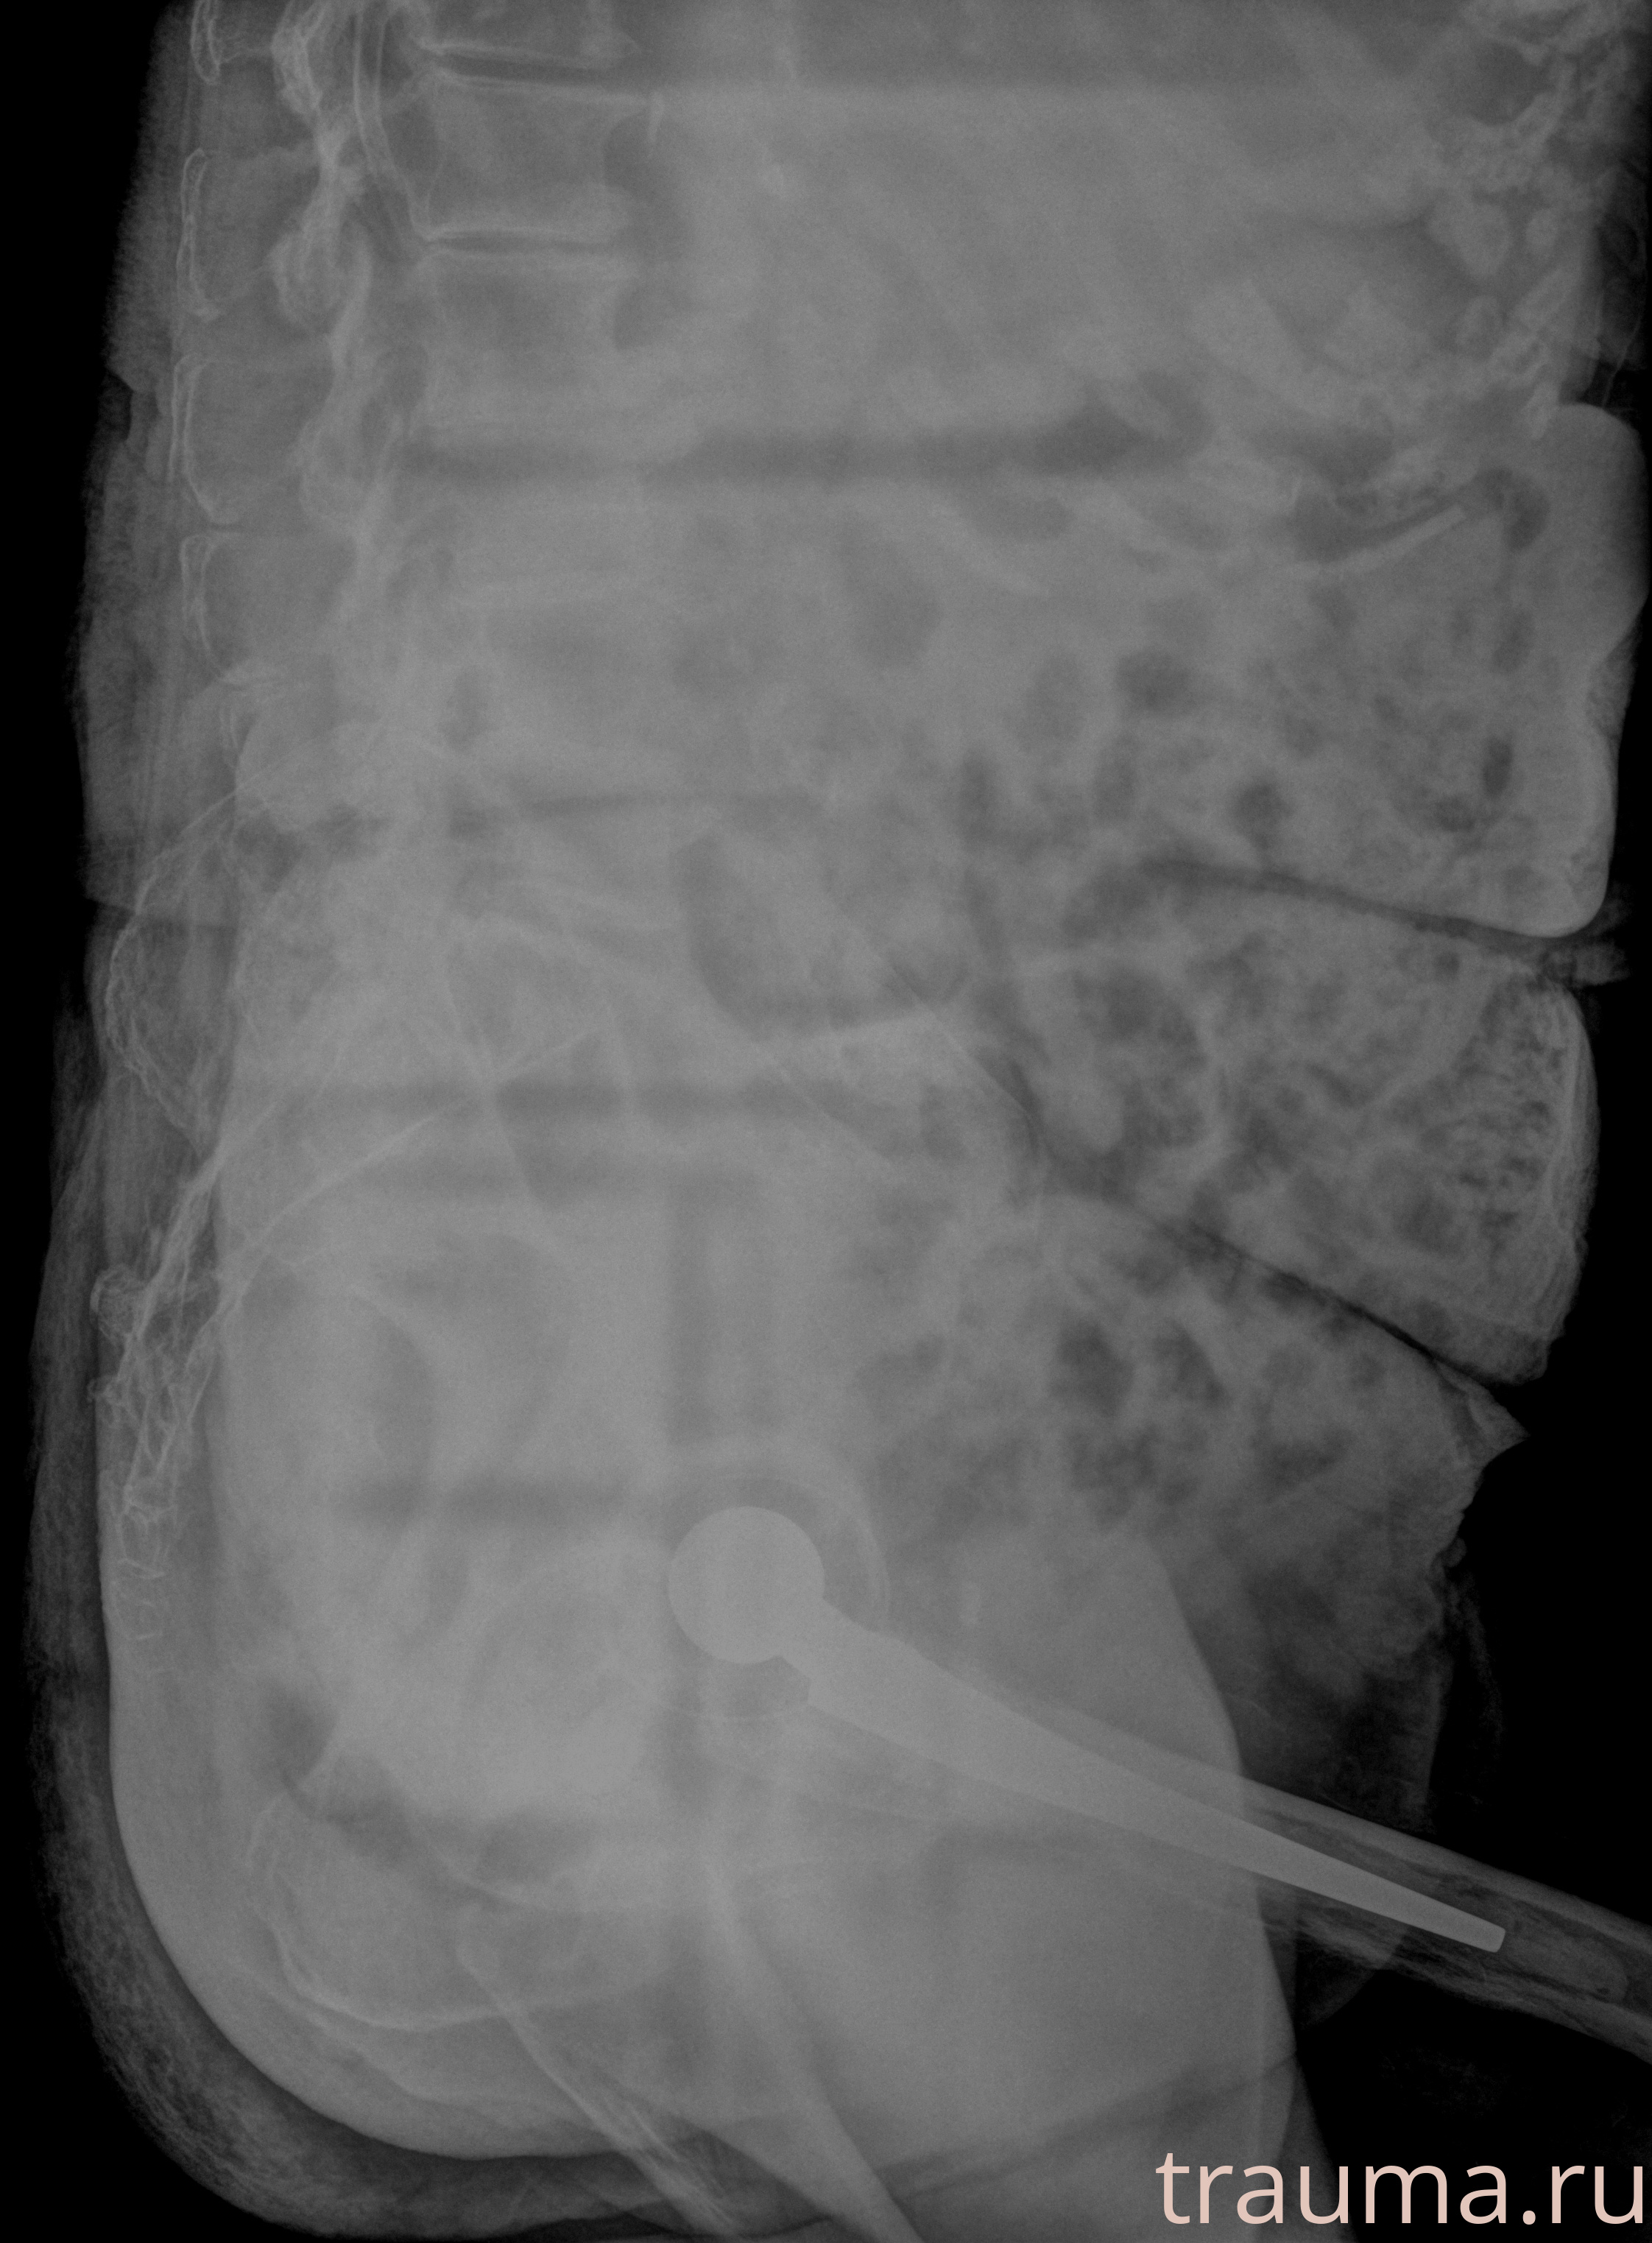

Рентгенограммы

Рентген на дому: по вашему адресу приезжает врач-рентгенолог, травматолог-ортопед с мобильным рентгеновским аппаратом, проводит диагностику травмы или заболевания, делает необходимые рентгенограммы, дает рекомендации по дальнейшему лечению. Получить качественные снимки в домашних условиях возможно благодаря уникальной методике, разработанной МосРентген Центром для института  Склифосовского

при переломе шейки бедра и пневмонии от компании МосРентген Центр - партнера Института имени Склифосовского